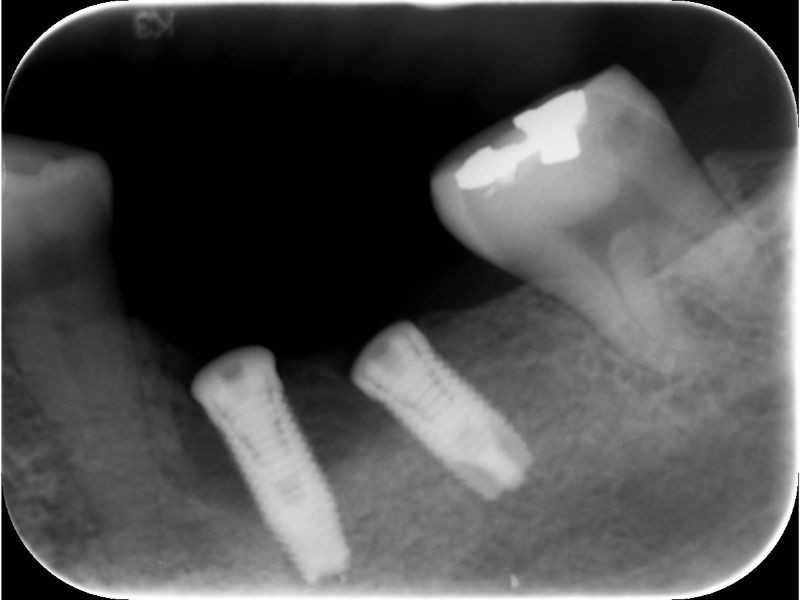

案例一